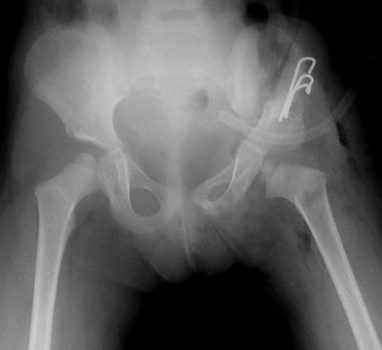

2. Открытое вправление бедра в сочетании с транспозицией вертлужной впадины (подвздошной остеотомией таза)

Применяется у детей старше 1 года в тех ситуациях, когда врожденный вывих бедра сочетается с выраженным недоразвитием вертлужной впадины.

Разработанная нами методика подвздошной остеотомии не требует использования трансплантата. То есть, при фиксации фрагментов остеотомии тазовой кости нет необходимости в использовании чужеродных тканей или заборе собственного костного трансплантата.

«Способ хирургического лечения детей с патологией тазобедренного сустава» (патент РФ на изобретение № 2405486 от 10.12.2010 г.)

3. Открытое вправление бедра в сочетании с подвздошной остеотомией таза по Salter и укорачивающей корригирующей (деторсионно-варизирующей) остеотомией бедра

В тех случаях, когда головка бедра смещена высоко относительно впадины, помимо собственного открытого вправления бедра возникает необходимость вмешательства как на тазовой, так и на бедренной кости - т.н. «классическая триада».

Операция применяется у детей от 2 до 6-7 лет и позволяет обеспечить хорошие отдаленные результаты лечения у большинства пациентов.